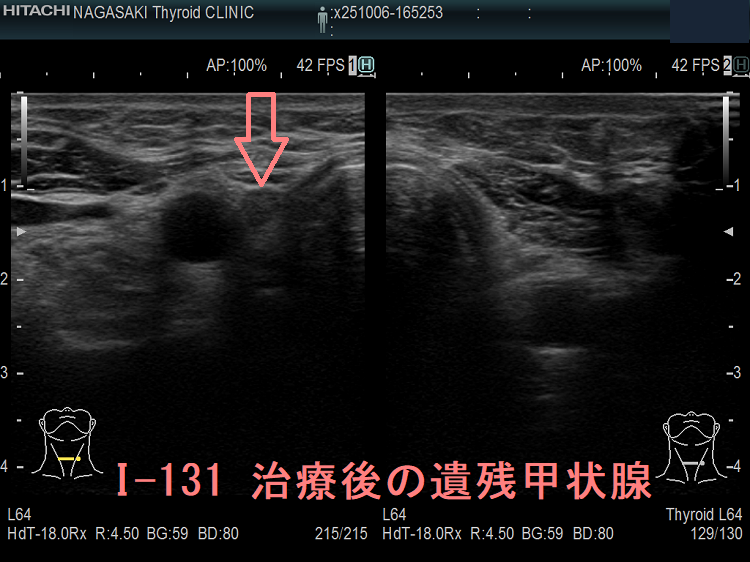

しかし、甲状腺癌細胞のヨウ素(ヨード)取り込み能力は、正常甲状腺細胞の1/10~1/100程度しかないので、正常な甲状腺組織が残っていると放射性ヨウ素(I-131)は正常甲状腺細胞にだけ集まり、甲状腺癌細胞に取り込まれません。

よって、甲状腺全摘手術した後で、甲状腺癌細胞しか残っていないのが、放射性ヨウ素(I-131)治療を行う条件です。

甲状腺分化癌(乳頭癌・濾胞癌)全摘手術後は、甲状腺床(甲状腺をはく離した部位)の残存細胞を完全に消滅させるため30mCi(1,110MBq=1.1GBq)のI-131 アブレーション治療を外来で行う場合があります[残存甲状腺破壊を目的としたI-131(1,110MBq)による外来治療実施要綱]。

正常甲状腺細胞が完全に消滅し、サイログロブリンを産生するのは甲状腺癌だけになるため、腫瘍マーカーとしての血清サイログロブリン値の解釈が容易になり、術後の再発診断に役立ちます。